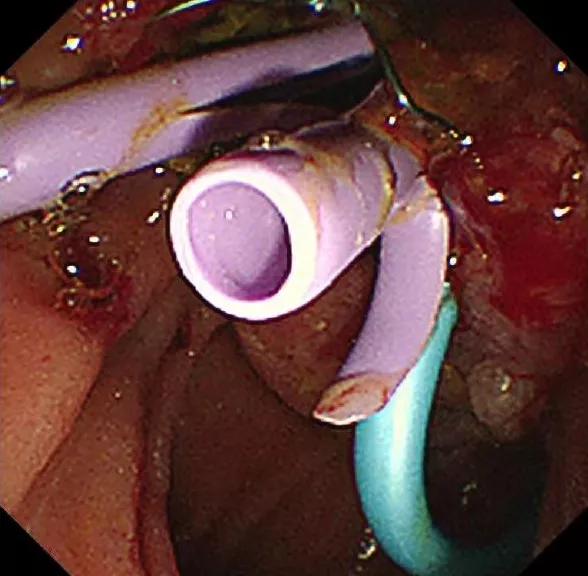

8月28日,在麻醉科等科室的全力配合下,普外科付云强为主任为患者实施手术,术中付云强主任将十二指肠镜经口腔进入十二指肠,在十二指肠主乳头的方寸之间,细心的寻找胰管开口,功夫不负有心人,在其精湛的技术下,顺利的找到并放置了胰管支架,再经十二指肠乳头开口处注入造影剂行胆管造影,造影显示胆总管全程有充盈缺损,考虑肿瘤胆道系统广泛转移,术中诊断为壶腹部癌ERCP术后,胆总管及肝内转移。根据治疗计划行十二指肠逆行胰胆管造影术+原胆道支架拔除+胆道清理+胆道支架内引流术。手术顺利,术后患者安返病房。